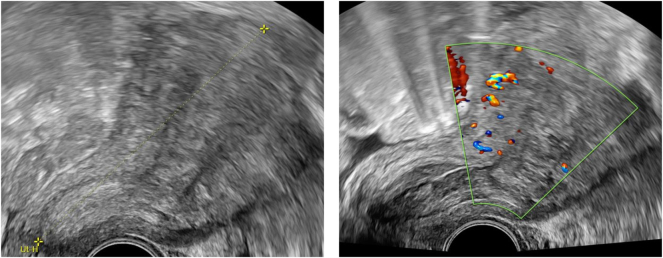

Case presentation: A 38-year-old woman (2 Gravida, 2 Para) presented at our clinic four weeks after her second cesarean section with persistent vaginal bleeding and decreasing hemoglobin to 6.8 mg/L. In the ultrasound examination, retained placental tissue was suspected. Since conservative management with misoprostol was not effective, a curettage was performed. The histopathological result revealed a gestational choriocarcinoma invading the myometrium (CK18 positive, HPL positive, beta-hCG positive, p63 negative, PLAP positive, Ki67 (MIB-1)>80 %). Beta-hCG was 50,607 IU/L at the time of diagnosis. The computed tomography (CT) scan revealed bilateral pulmonary metastases. There were no metastases to the liver, lymph nodes, skeleton or brain. In accordance with FIGO recommendations [stage III, Score 8 (high risk) choriocarcinoma] a multi-drug chemotherapy after EMACO-regimen was started 9.5 weeks postpartum during 14 days for seven cycles. The patient has been in tumor remission since then.

Abstract Image